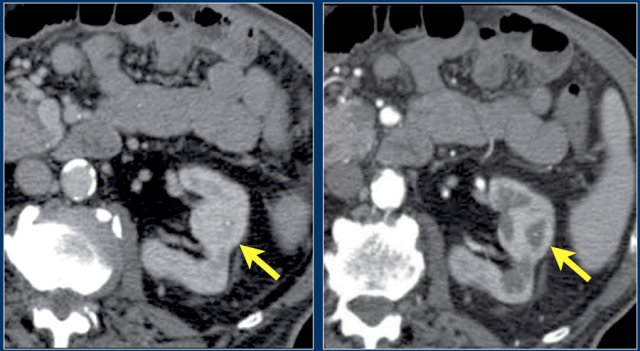

Here another patient with lymphoma located in the mediastinum, pancreas (arrow) and in both kidneys.

Here a patient with lung cancer.

There is a metastasis in the left kidney and there are multiple lymph node metastases (arrows).

If this was the only presentation, it would be difficult to differentiate from a renal cell carcinoma with lymph node metastases.